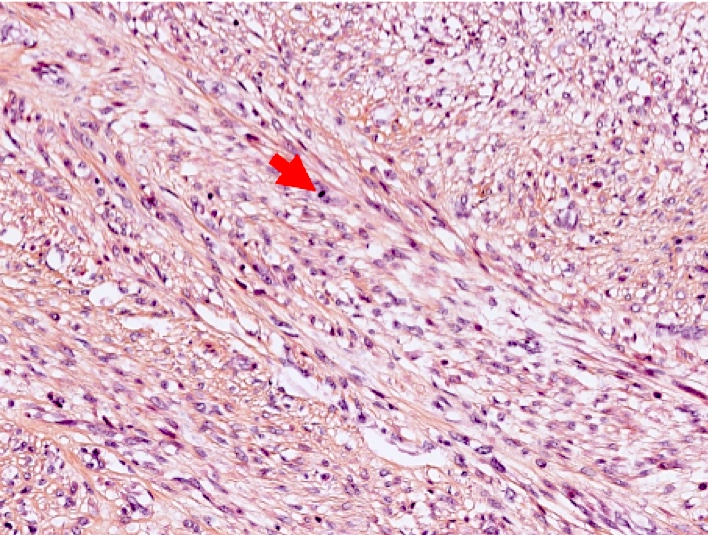

- Leiomyoma with bizarre nuclei:

- Bizarrely shaped, hyperchromatic, multilobulated nuclei with nuclear pseudoinclusions

- Arranged in a multifocal to diffuse distribution in a background of a typical leiomyoma (Am J Surg Pathol 2014;38:1330, Mod Pathol 2017;30:1476, Am J Surg Pathol 2016;40:923, Cancer 2014;120:3165, Am J Surg Pathol 1997;21:1261)

- Alveolar edema, staghorn vessels

- Low mitotic activity (< 5 mitoses/10 high power fields)

- Absence of tumor cell necrosis

- Vasculature variable (staghorn vessels, thick walled vessels, fibrinoid necrosis of vessel walls, luminal vascular obliteration)

- Diagnostic key: intermixed normal spindled smooth muscle cells